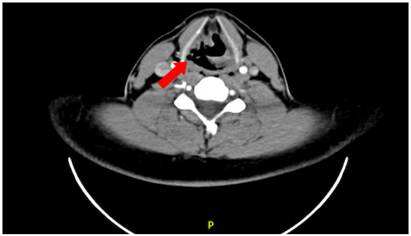

La sensibilidad, especificidad, valor predictivo positivo (VPP) y valor predictivo negativo (VPN) para el diagnóstico de lesiones aerodigestivas por TC se presentan en la Tabla 2. En un paciente se observó lesión de vía aérea en TC, confirmada mediante fibrobroncoscopia, la cual consistía en una lesión laríngea a nivel del hioides (Figura 2), como consecuencia de una colisión en motocicleta con trauma cervical directo, que fue manejada de manera conservadora. En otro paciente se identificó en TC una lesión esofágica, confirmada mediante EDS, consistente en dos desgarros lineales a nivel del esófago torácico, que requerían manejo quirúrgico; en este mismo paciente se evidenció una lesión de la tráquea durante la cirugía de reparación esofágica, no visualizada en TC ni en la fibrobroncoscopia, aun luego de revisar las imágenes de forma retrospectiva, por lo que se sospechó una lesión traqueal externa sin pérdida de la solución de continuidad. Ambas lesiones fueron consecuencia de una colisión de alta energía en motocicleta, para un total de tres lesiones aerodigestivas en dos pacientes. En ningún otro paciente se evidenció lesión de vía aérea que no hubiese sido visualizada o sospechada en TC. No se encontró lesión esofágica en el esofagograma contrastado por TC.

Algunos signos radiológicos específicos pueden hacer sospechar la presencia de una lesión aerodigestiva 14. Las disrupciones focales o irregularidades de la pared traqueal o bronquial son altamente sugestivas de lesión de vía aérea, al igual que los patrones específicos de distribución del aire mediastinal, el cual suele estar distribuido de forma asimétrica, con mayor cantidad de aire del lado de la lesión y rodeándola. Los hallazgos tomográficos sugestivos de lesión esofágica son la presencia de aire extraluminal periesofágico, el derrame pleural izquierdo, el colapso del lóbulo pulmonar inferior izquierdo, la presencia de aire en el espacio prevertebral y la presencia de líquido en el compartimiento mediastinal visceral 2,5,15.